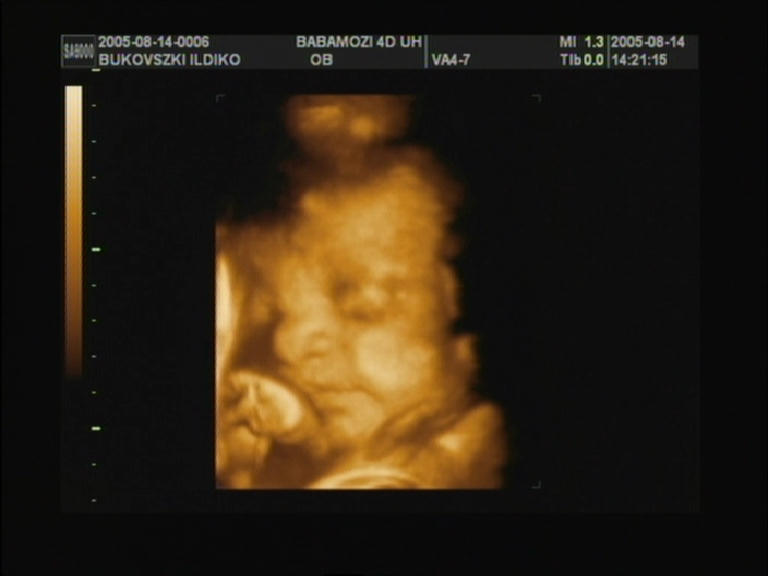

elkészült végre a 4D-s ultrahang is... ez lett a legjobb

kép... 30. hét |